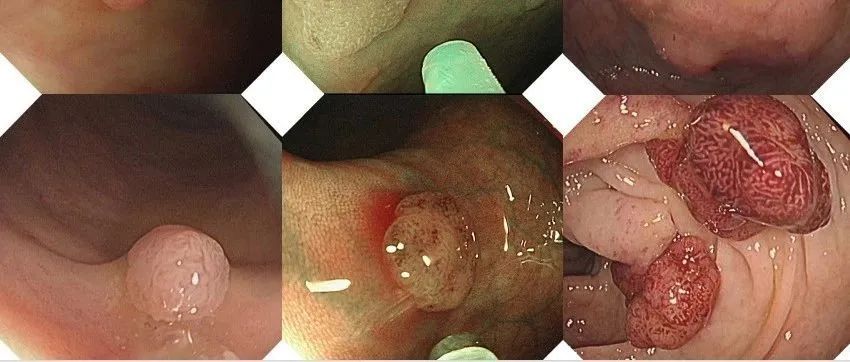

仅供医学专业人士阅读参考90后是如何虐胃的?早预防、早检查、早治疗什么是肠息肉?肠息肉就是肠道黏膜上所有隆起性的病变的总称,从结肠黏膜表面突出到肠腔的息肉状病变,通俗地说,就是肠道上长了一些肉疙瘩,人体的整个消化道都可以有息肉生长,其中以结肠和直肠息肉为最多,小肠息肉比较少。在未确定病理性质前均称为结肠息肉。息肉的病理学类型包括了肿瘤性和非肿瘤性病变。炎症性息肉、增生性息肉、错构瘤性息肉等,一般不会癌变,称为非肿瘤性;...

我们做肠镜检查,最常见的赘生物就是息肉,其中的腺瘤性息肉,其实就是肠癌的预备状态,90%以上的结直肠癌是它演变而来的。而腺瘤性息肉在50岁之后的检出率非常高。一项研究显示:在7203例次肠镜检查中,息肉检出率为:50岁前为17%,50~59岁为35%,60~69岁为56%,>70岁为63%。以上数据还不包括结肠息肉病、P-J综合征、进展期结肠癌、肠道准备不合格者及检查失败者。研究显示,直径超过2cm的腺瘤恶变率高达50%,多发性家族性息肉病癌变率可达100%,且发生癌变的年龄较轻。...

一文读懂肠息肉—— 为啥会长肠息肉?严重吗?如何治疗?怎样预防?【附手术视频】

本文作者:杨炳灿,华西厦门医院消化疾病中心本文原创:阿炳消化时间,欢迎关注01什么是肠息肉肠息肉是指从肠道黏膜表面突出到肠腔的隆起性病变,在未确定病理性质前均称做肠息肉。其发病率随年龄增加而上升,男性多见。根据病理可分为腺瘤性息肉和非腺瘤性息肉。腺瘤性息肉主要包括管状腺瘤、绒毛状腺瘤、管状绒毛状腺瘤,非腺瘤性息肉主要有增生性息肉、炎性息肉、错构瘤性息肉等。02息肉是否会癌变在所有肠癌中,80%~95%以上的肠癌都是由腺瘤性息肉慢慢演变发展而来的...